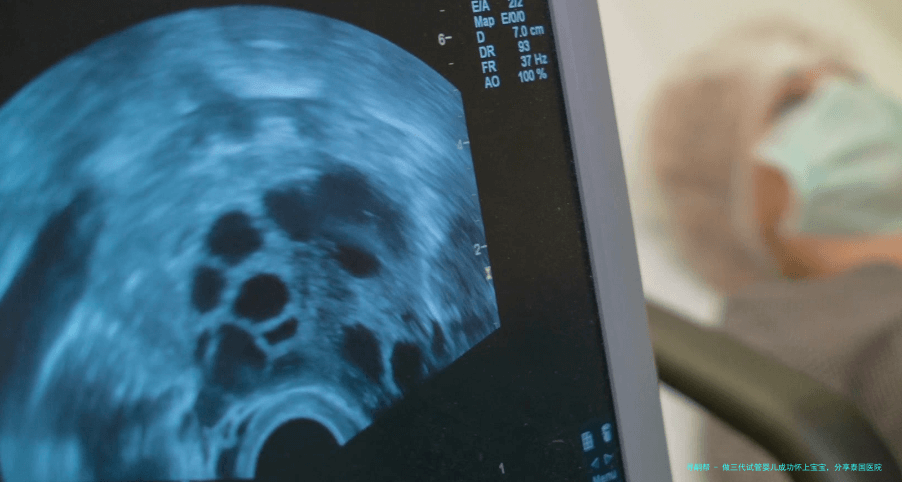

结果出来后见医生,医生给做阴道B超,护士给了一个小裙子更换上,很人类本性化,如此避免了很多小尴尬。

医生问的很仔细,全程看着我,很重视我讲述的每一个细节,反复问清晰。医生说我的子宫情况非常好,基础卵泡有5个,加上还要选� ,年龄大,就看能不能得到正常的胚胎。